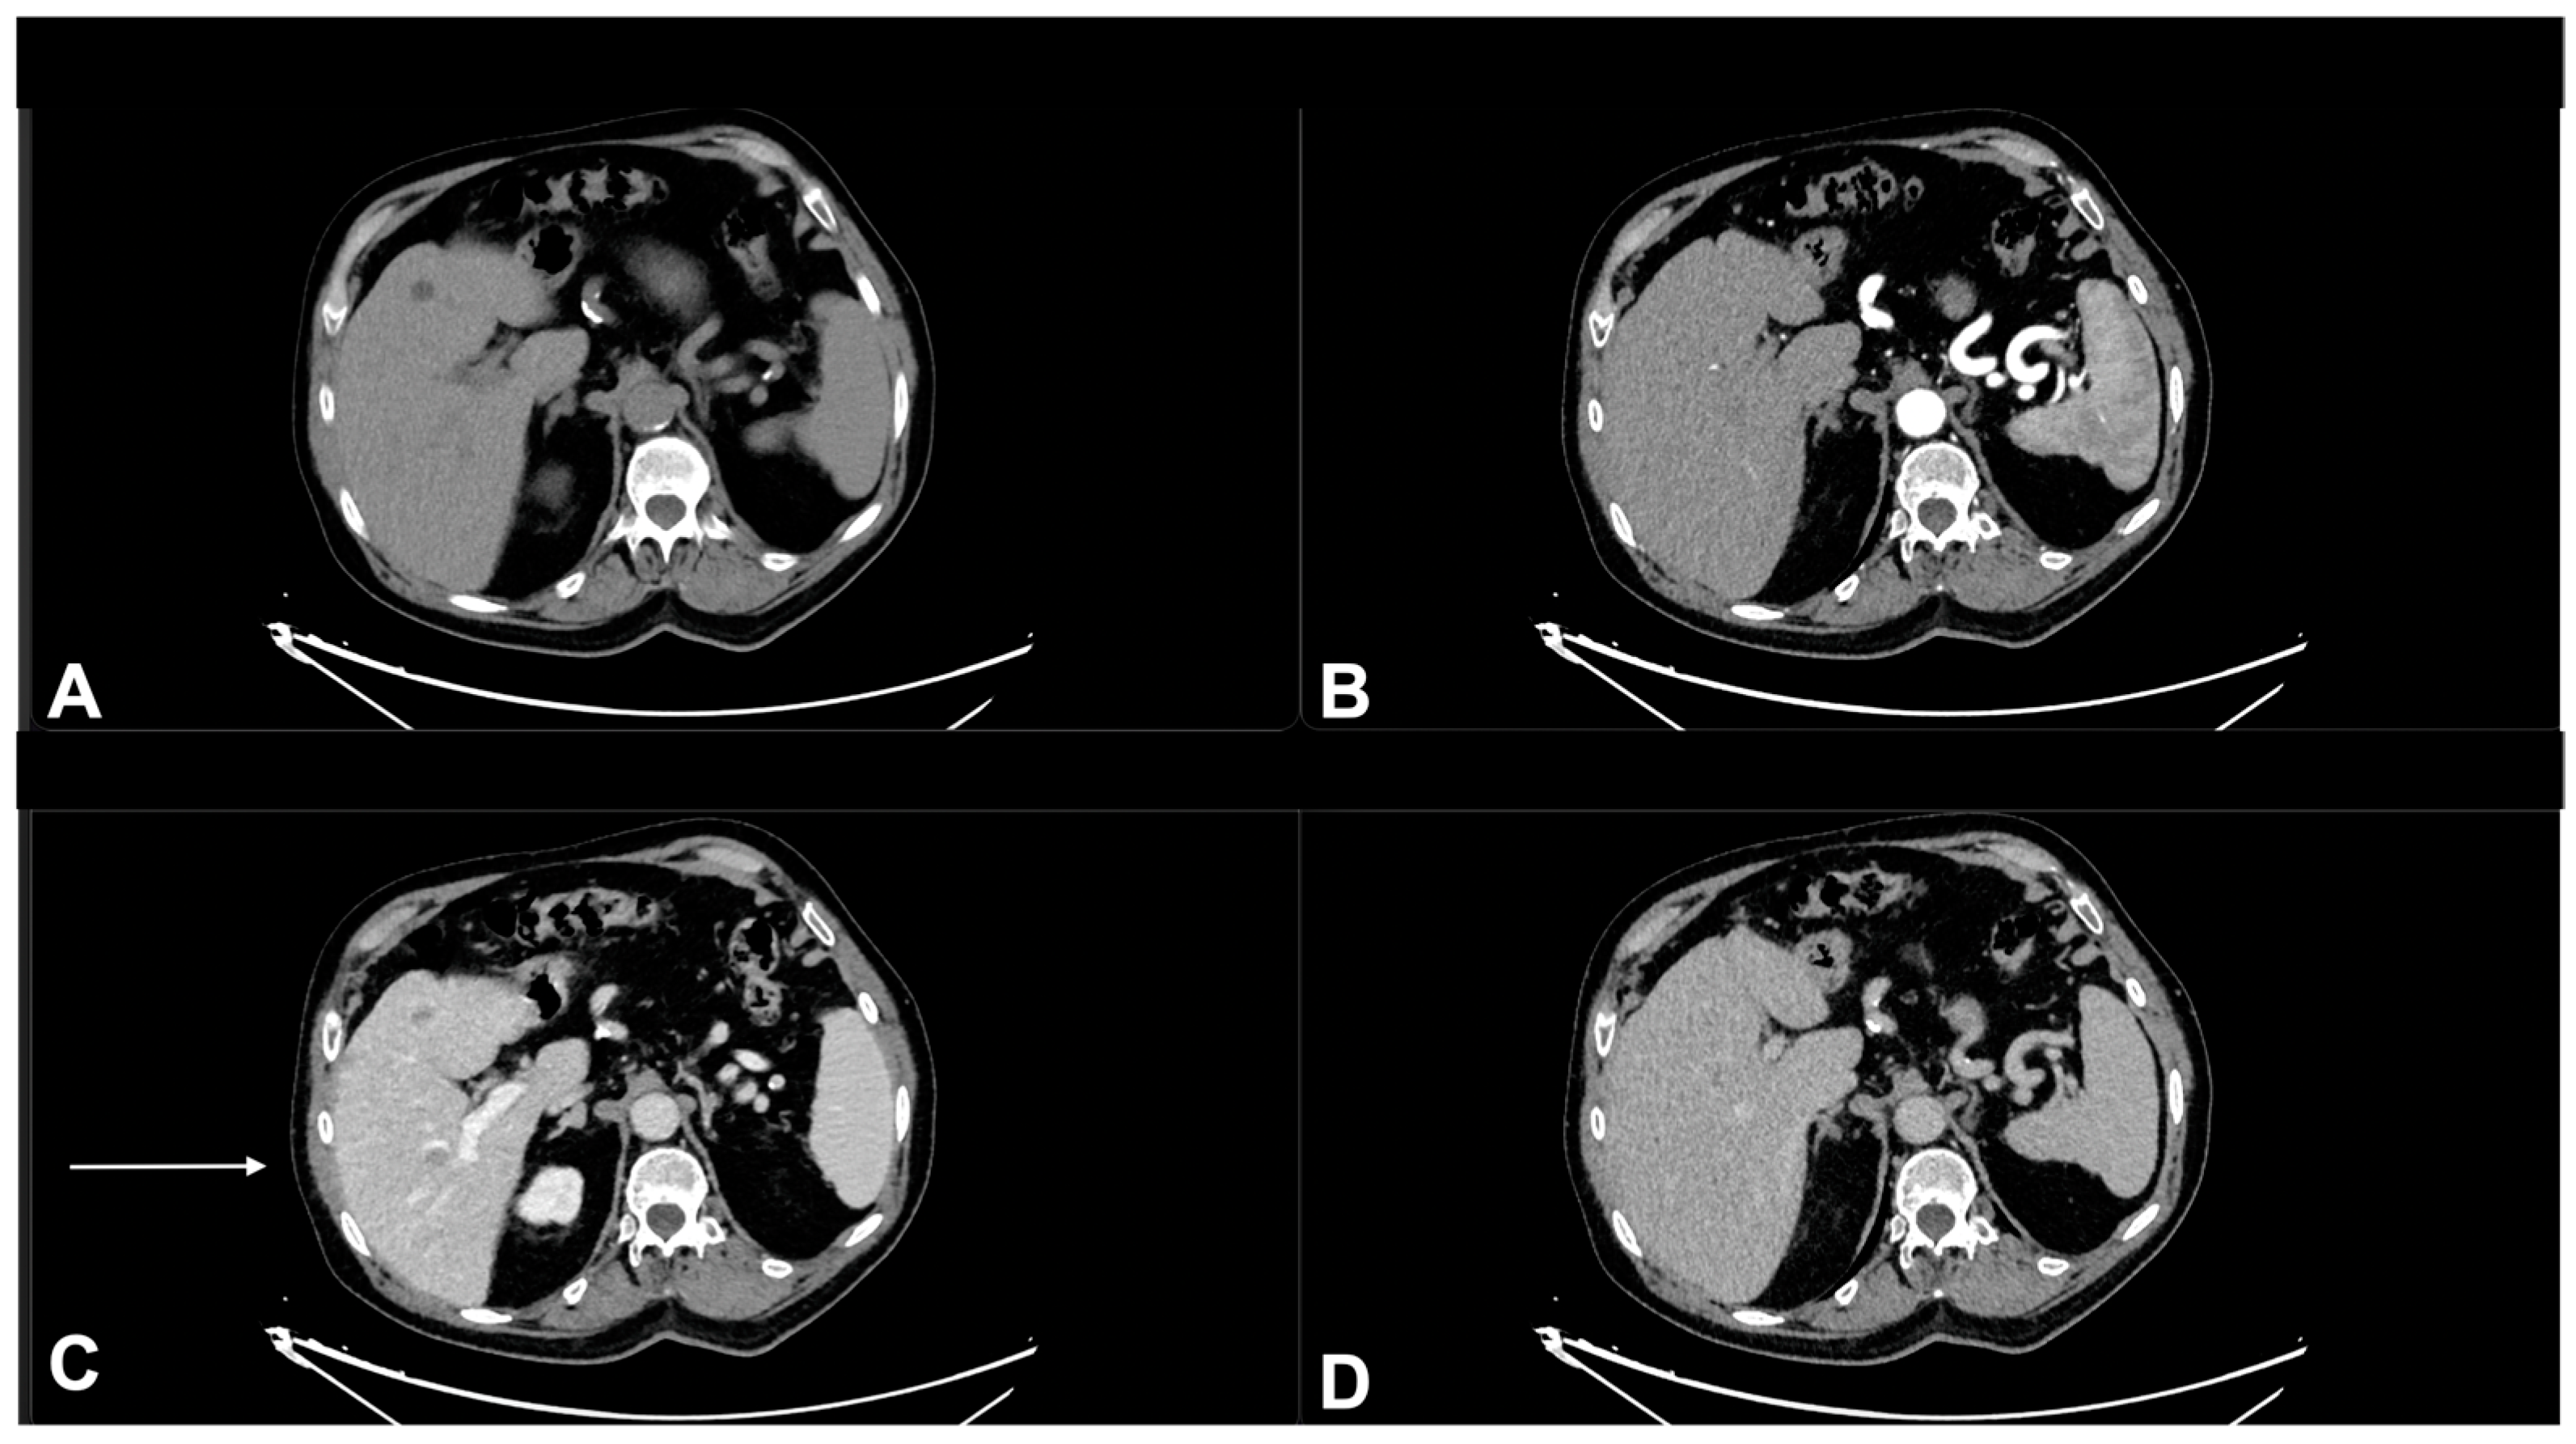

- Granata, V.; Fusco, R.; Piccirillo, M.; Palaia, R.; Petrillo, A.; Lastoria, S.; Izzo, F. Electrochemotherapy in locally advanced pancreatic cancer: Preliminary results. Int. J. Surg. 2015, 18, 230–236. [Google Scholar] [CrossRef] [PubMed]

- Granata, V.; Fusco, R.; Setola, S.V.; Piccirillo, M.; Leongito, M.; Palaia, R.; Granata, F.; Lastoria, S.; Izzo, F.; Petrillo, A. Early radiological assessment of locally advanced pancreatic cancer treated with electrochemotherapy. World J. Gastroenterol. 2017, 23, 4767–4778. [Google Scholar] [CrossRef] [PubMed]